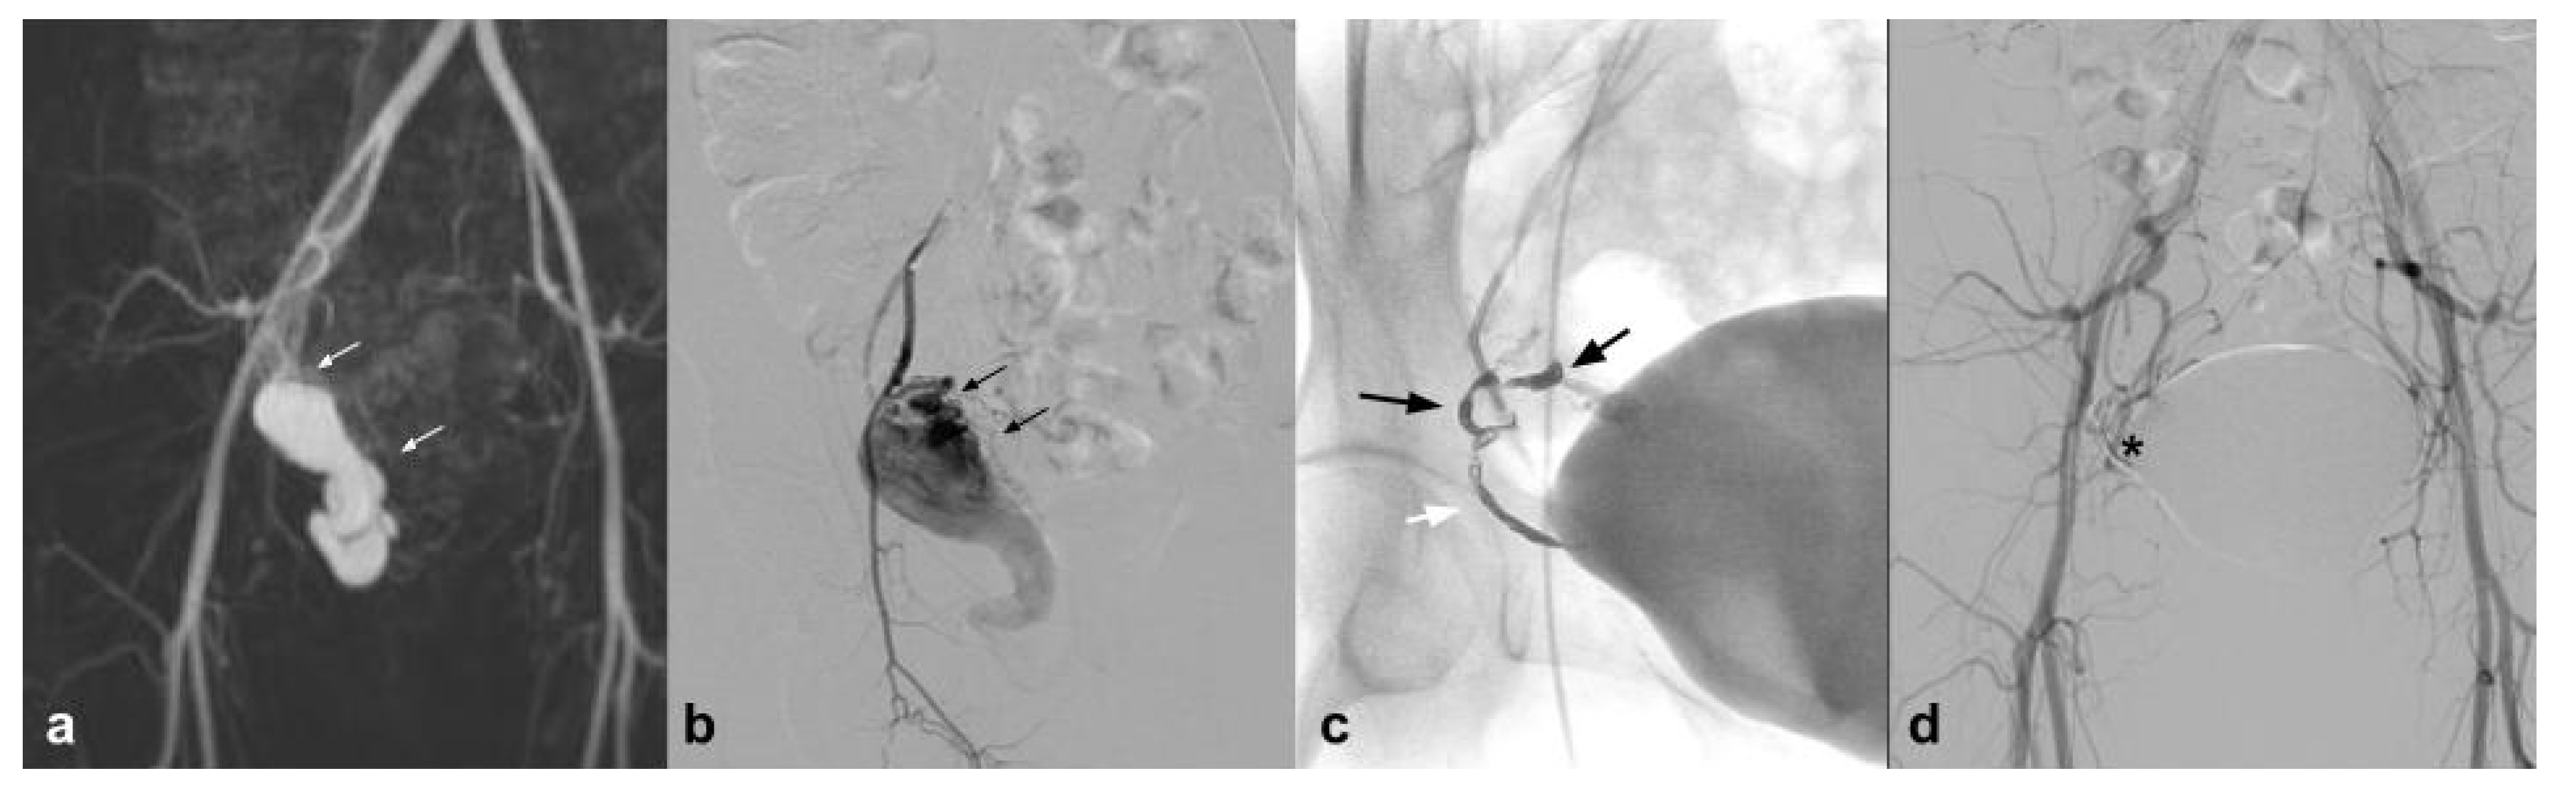

This new generation of embolizing agents has further advantages, excellent embolizing capacity of the treated vessel, and is able to reach vessels with a diameter of 80 microns (Figure 2).

Figure 2.

(a) Coronal CTA MIP demonstrates hypertrophic bronchial artery with tortuous course originating at 9:00 from the convexity of the aortic arch (white arrows); (b) DSA performed with Simmons 1 catheter at the level of the ostium of the bronchial artery confirms the presence of the hypertrophic vessel (black arrow) with a small tributary branch of the right upper lobe (arrow head); (c) single-shot fluoroscopy after embolization shows the presence of the microcatheter at the level of the proximal portion of the bronchial artery, with a Squid 12 cast completely occupying the main trunk (white arrows); (d) post-procedure DSA control demonstrates complete exclusion of the treated vessel (asterisk) with patency of the small branch for the right pulmonary upper lobe (white arrow).

Figure 3.

(a) Axial CTA shows, the presence of Type II endoleak after EVAR, supplied by lumbar arteries (white arrow). (b) DSA performed with microcatheter positioned in a lumbar branch through the ilio-lumbar artery highlights the presence of hypertrophic lumbar circles (white arrow head) with sac refuelling (white arrow). (c) Post-procedure DSA shows the cast of Squid 12, which completely occupies the space of the endoleak in the sac (white arrow).